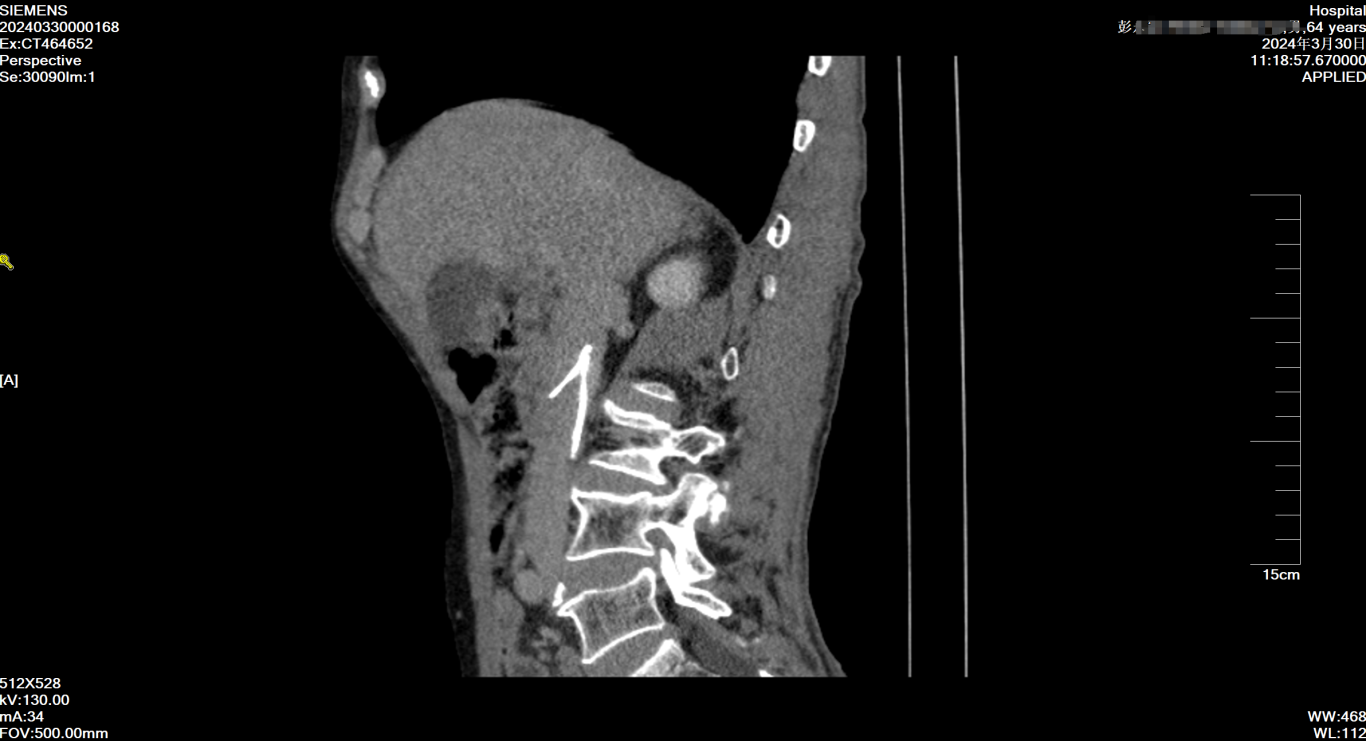

患者彭某某到我院就诊,完善相关检查后诊断为:急性肺栓塞、下肢静脉血栓形成,于2023年12月19日在局麻下行下腔静脉滤器置入术,术后患者好转出院,目前,下腔静脉滤器置入术后3月余,前来我院就诊复查下腔静脉情况,于是联系放射科上海援滇专家唐纳(放射科执行主任),在放射科成功完成了下腔静脉CTV+三维重建影像检查,下腔静脉CTV+三维重建影像检查能重点关注下腔静脉滤器有无血栓形成及滤器位置、形态情况。为临床医师提供了精准而直观的影像资料及治疗方案。最终临床相关科室安全成功完成下腔静脉滤器取出术,无任何并发症。